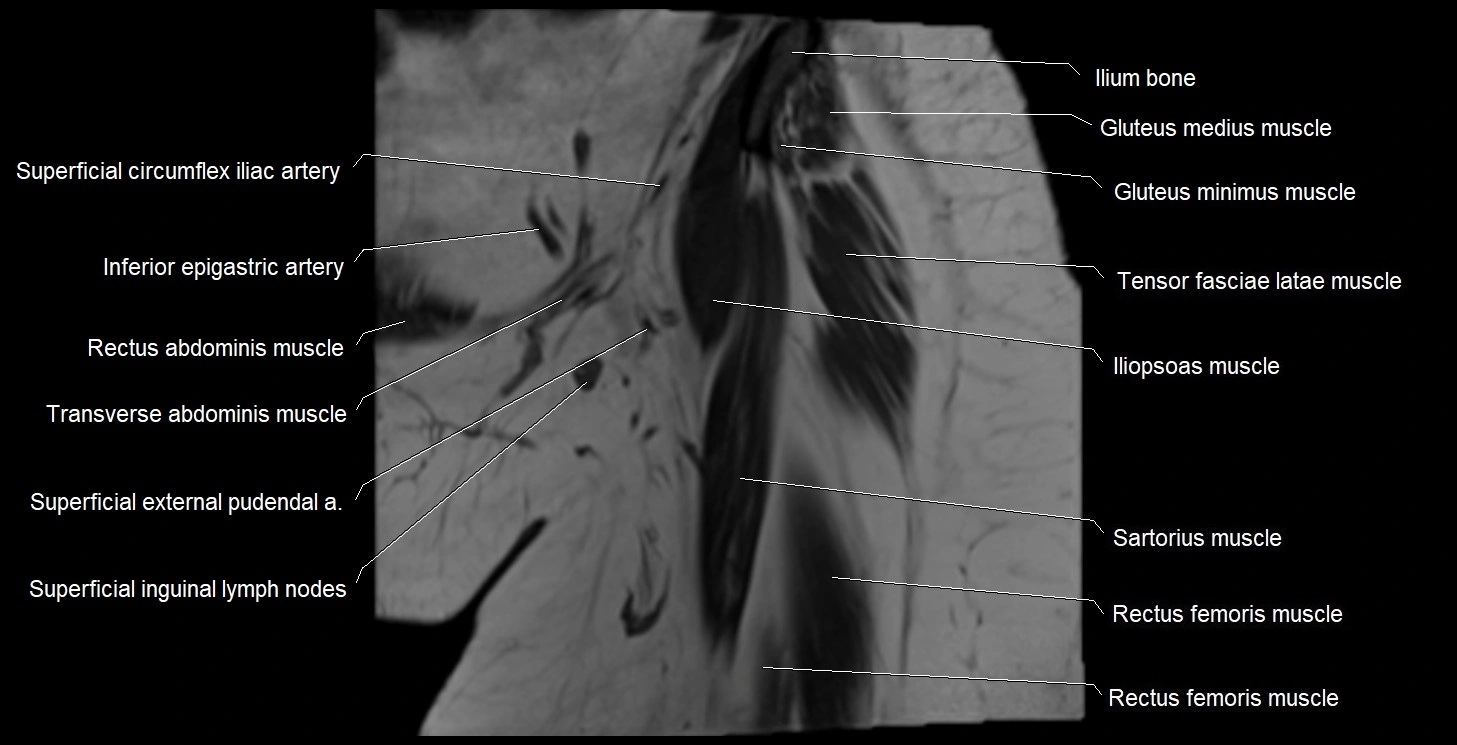

- Gluteus medius muscle

- Gluteus minimus muscle

- Iliopsoas muscle

- Inferior epigastric artery

- Rectus femoris muscle

- Sartorius muscle

- Superficial circumflex iliac artery

- Superficial inguinal lymph nodes

- Tensor fasciae latae muscle